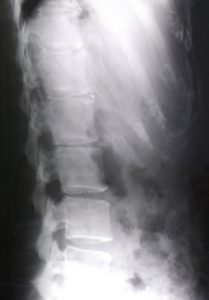

腰椎分離症・腰椎分離すべり症と腰痛の関係|画像と症状を正しく理解する